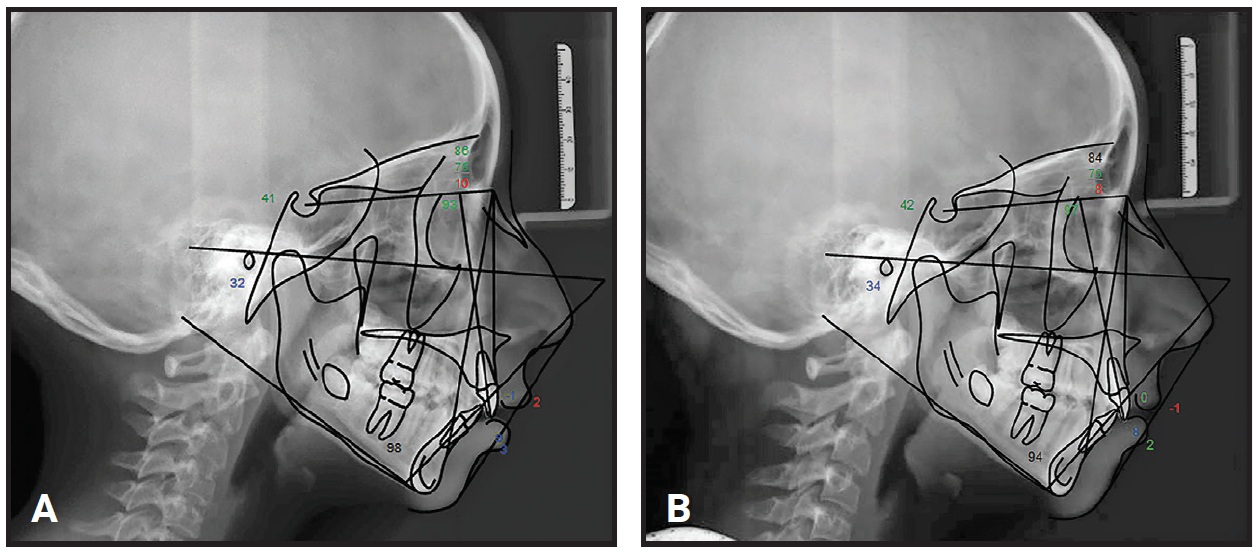

Cephalometric radiographs were taken at each time point: initial (T1), end of MA (T2), and post-treatment (T3). The cephalograms were randomized before being traced by an external academic institution. The T1, T2, and T3 radiographs were imported into Dolphin Imaging‡ version 11.8, where landmark location and superimpositions were performed (Fig. 2). Student’s paired T-test was used to evaluate the cephalometric parameters; based on the Bonferroni correction for 24 parameters, statistical significance was set at a level of < .002.

Fig. 2 Sample cephalometric tracings. A. Pretreatment (T1). B. End of MA phase (T2).